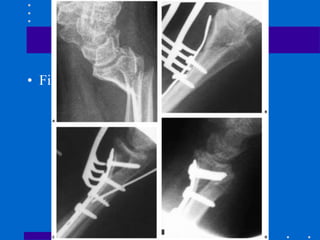

Fixação interna - Placa dorsal

• Vantagens:

• abordagem evita estruturas neurovasculares

palmares

• apoio é no local de compressão da maioria

das fraturas

• Desvantagens:

• tendinite extensores ou ruptura,

particularmente no tubérculo de Lister

• parafusos distais tem de ser orientados

palmar e proximal, isto permite

deslocamento palmar de fragmentos -

incongruência ARUD e mais proeminência

dorsal www.traumatologiaeortopedia.com.br

• Figura 26 -24

• Fig 26 -24